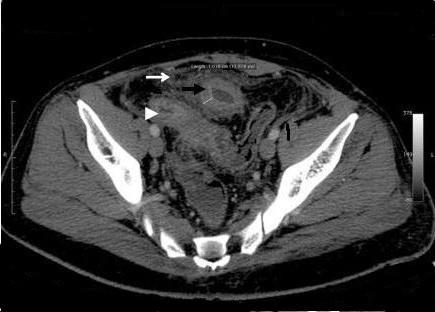

A 38-year-old Caucasian Greek man presented with a subtle and delayed small bowel obstruction caused by a post-traumatic ileosigmoid fistula and ileal stricture four months after a road traffic accident.

一名38岁的高加索希腊男子,在道路交通事故四个月后,因创伤后回肠乙状结肠瘘和回肠狭窄,出现了轻微且延迟性的小肠梗阻。